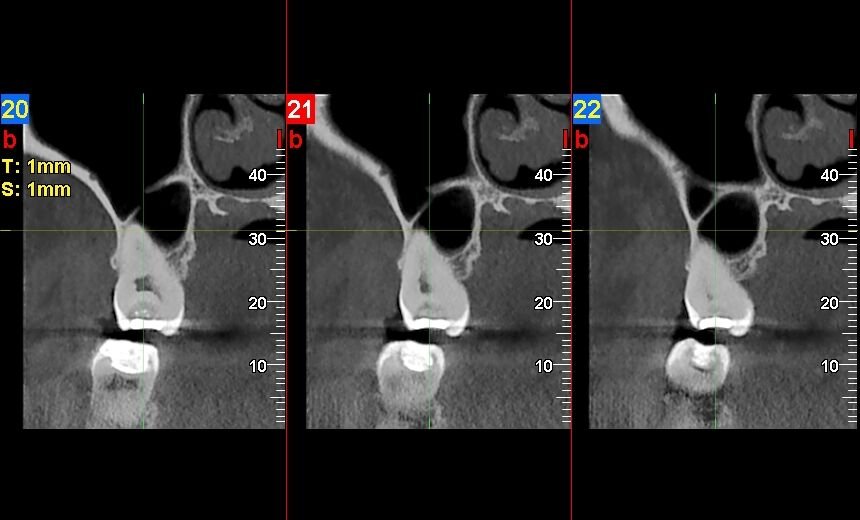

Un examen TAC cervical, también conocido como tomografía computarizada de la columna cervical, es una prueba de diagnóstico por imagen no invasiva. Utiliza un equipo especializado que emite haces de rayos X y un detector que gira alrededor del cuello, registrando la forma en que los tejidos absorben los rayos Un ordenador procesa esta información para crear imágenes transversales, o «rebanadas», de la región cervical. Estas imágenes se pueden reconstruir en 2D o 3D, ofreciendo una visión detallada de las vértebras, médula espinal, vasos sanguíneos y otros tejidos en el cuello. A diferencia de una radiografía convencional, que produce una imagen plana, un TAC proporciona una visión mucho más completa para identificar anomalías.

Además de las lesiones traumáticas, el TAC cervical es excelente para identificar una variedad de problemas degenerativos o congénitos en la columna vertebral. Esto incluye la espondilosis cervical, donde el desgaste de las articulaciones provoca la formación de espolones óseos (osteofitos) que pueden comprimir la médula espinal o las raíces nerviosas. Las hernias discales, donde el material del disco intervertebral se desplaza y aprieta las estructuras nerviosas, también se visualizan bien con esta técnica. La estenosis espinal cervical, un estrechamiento del canal que aloja la médula espinal, puede ser diagnosticada y su grado de severidad evaluado.

Un examen TAC cervical, también conocido como tomografía computarizada cervical, es una prueba de diagnóstico por imágenes que utiliza rayos X para crear imágenes detalladas de la región cervical, incluyendo la columna vertebral, los tejidos blandos y los vasos sanguíneos.